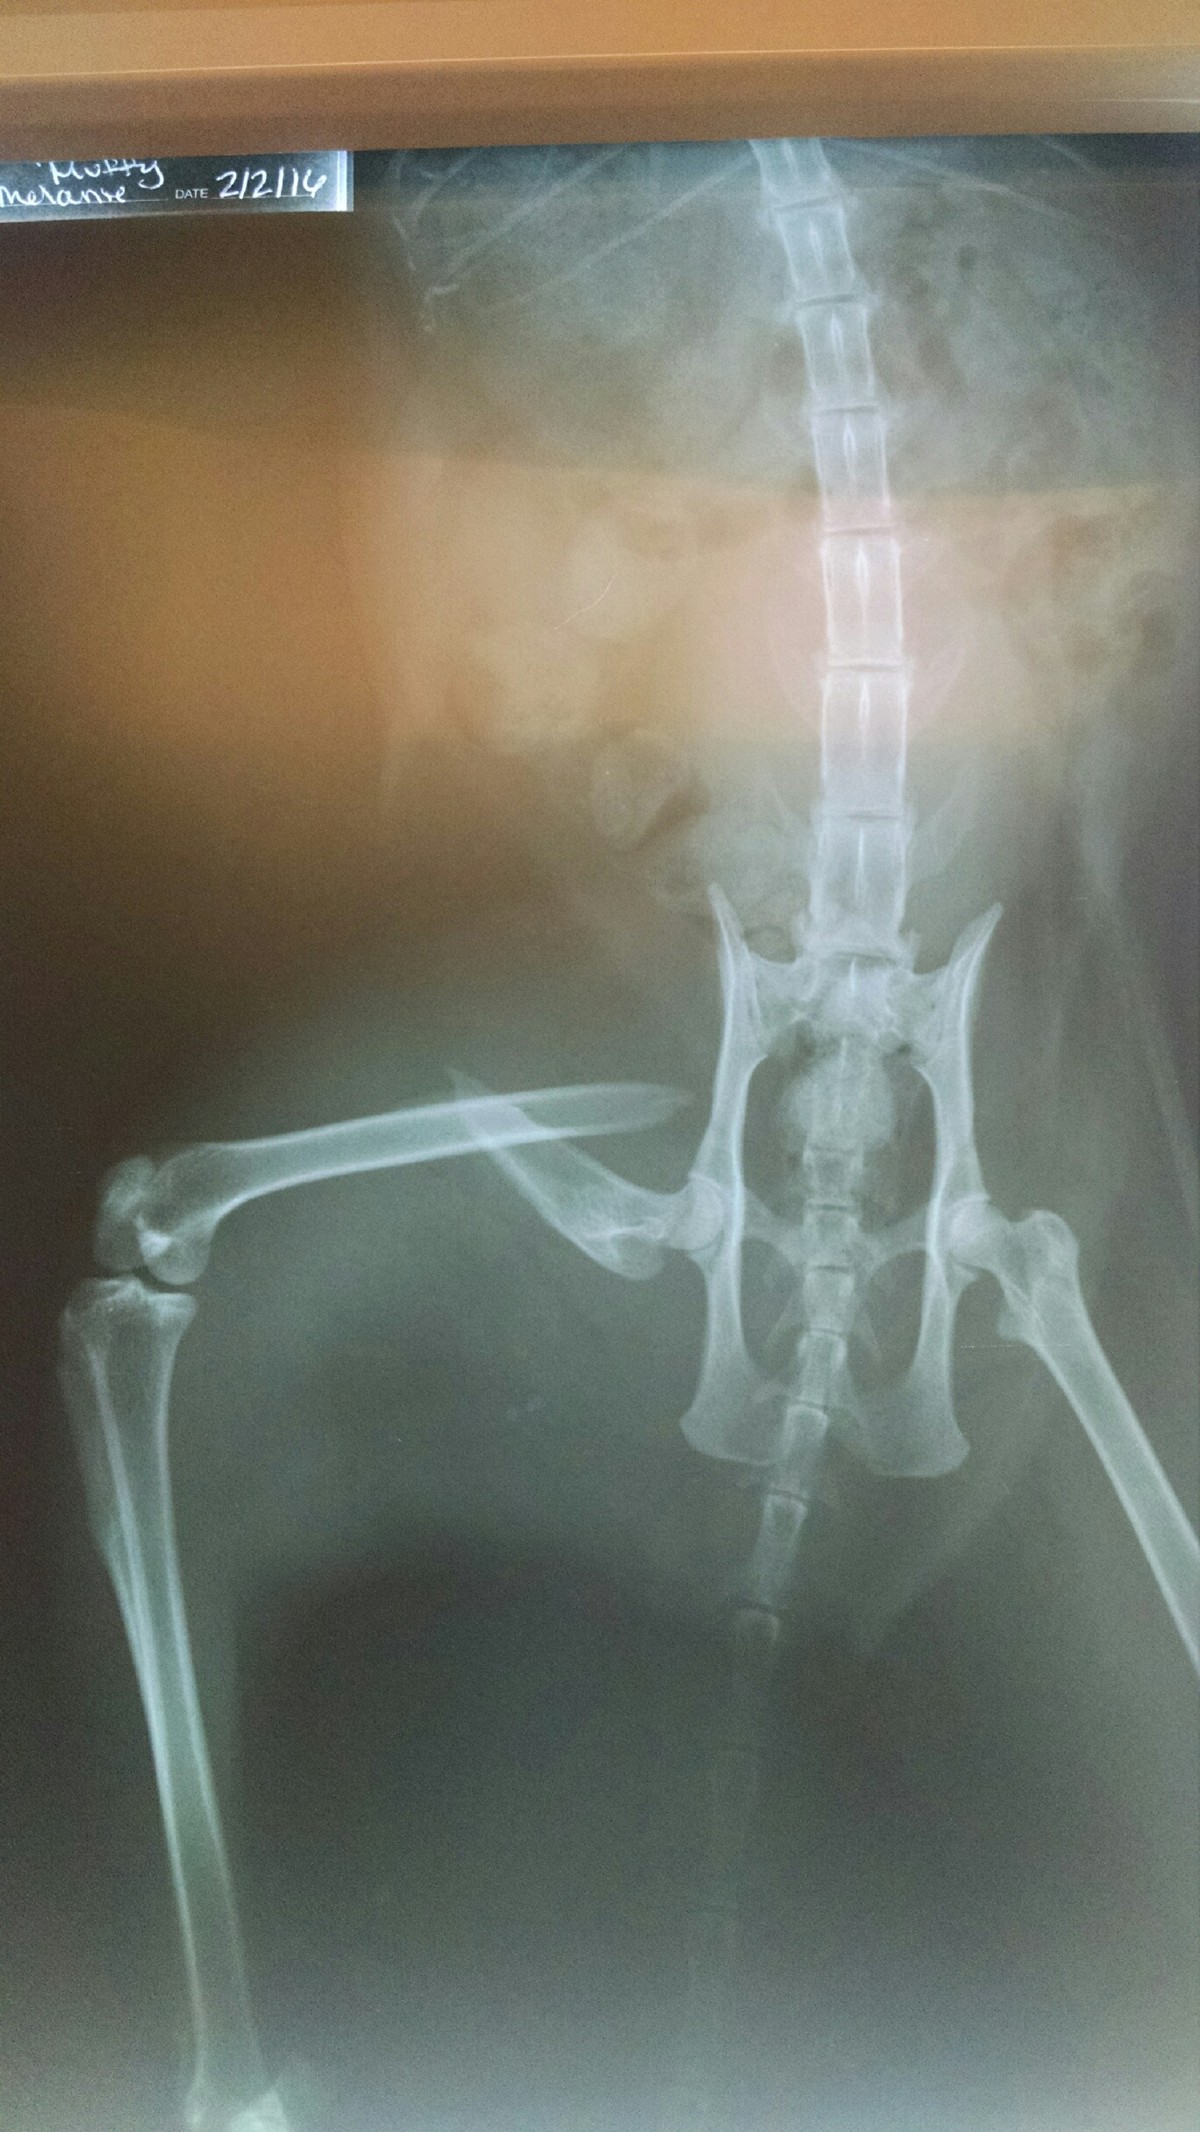

I really don't much like this new photo we got this week

IMG_20160202_102718620_3.jpg

how'd the poor critter bust his leg ??

Oh, Terry, I am so sorry and sad for both you and "Muffy."

Condolences from my Muffy to yours, Terry, and hopes for a speedy recovery.

She hasn't had morphine since last week. The last couple days we let her out of solitary when we could keep an eye on her. We have to watch that the big boys don't mess with her or she tries to jump up on stuff.

She has been seen scratching herself with the bum leg. She jumped onto a chair. Not too much of a limp. Lost a lot of weight.